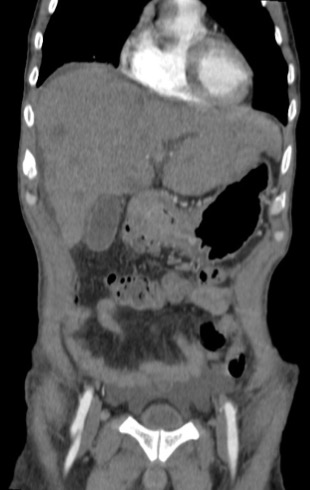

Gastric abnormalities show nonspecific gastrointestinal symptoms and similarly radiological findings. Intra and extra luminal gastric wall thickening are the most common finding in benign and malignant pathologic process. This aim of this case report was to describe several characteristics such as the location and size of the lesion, involvement of the gastric wall and surrounding structures, calcifications, and contrast enhancement pattern which can assist in radiological diagnosis. Several cases at our institution have similar gastrointestinal complaints, however, there were different lesions characteristic found in contrast enhanced abdominal CT scan. The first case 72-years-old man experienced hematemesis with radiologic finding diffuse gastric mucosal thickening as well as homogenous contrast enhancement but without calcification. The second case 37-years-old man complaint dizziness and melena with radiologic finding large tumor more than 10 cm in size, amorph calcification and heterogenous contrast enhancement. The last 60-years-old man case experienced melena and hematemesis, from abdominal CT scan showed irregular gastric mucosal thickening with heterogenous contrast enhancement and fat stranding around the lesion, without calcification. Methods used in these cases were contrast-enhanced abdominal CT scan, esophagogastroduodenoscopy (EGD), and biopsy in order to determine the diagnosis. Contrast-enhanced abdominal CT scan plays a vital role in describing the lesion characteristics which affects the determination of treatment options and future prognosis.